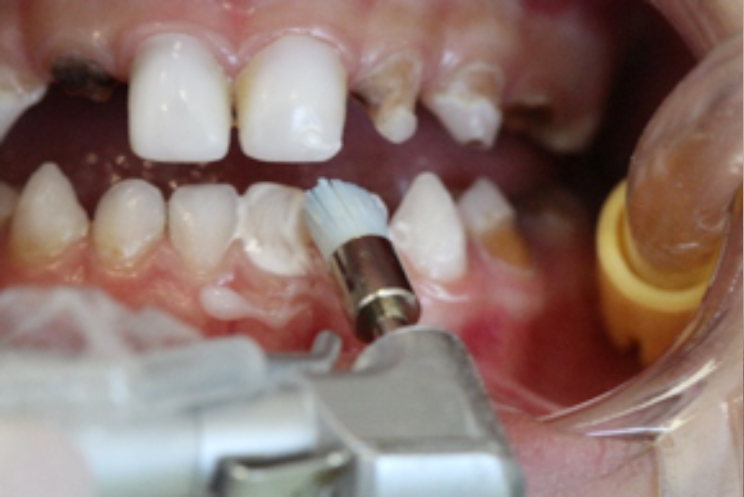

Inicialmente realizou-se a profilaxia com o uso de pasta profilática (sem flúor) e escova Robson. (foto 6)